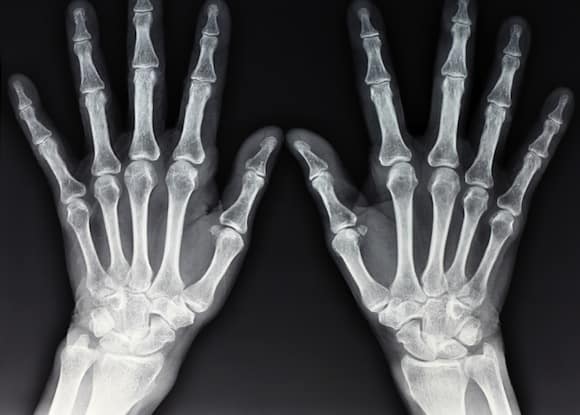

If the doctor thinks you’ve broken a bone, they’ll send you to get an X-Ray image. As you probably know, this is a way of getting a picture of what’s going on inside your body. X-Rays are a very cool kind of wave. Unlike light, they can pass through your body.

That’s right. X-Ray waves generally pass through your body, through your skin and soft tissues to the other side where they are recorded using special machinery. When the X-Rays go all the way through, they create a black image.

But when X-Rays hits objects like bones or organs such as your kidneys, the waves are blocked and a white image is created. And that’s how you get those black and white X-Ray images!